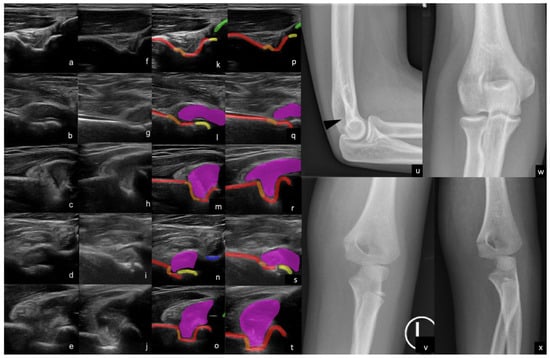

2.4. Ultrasound

2.5. Radiographs